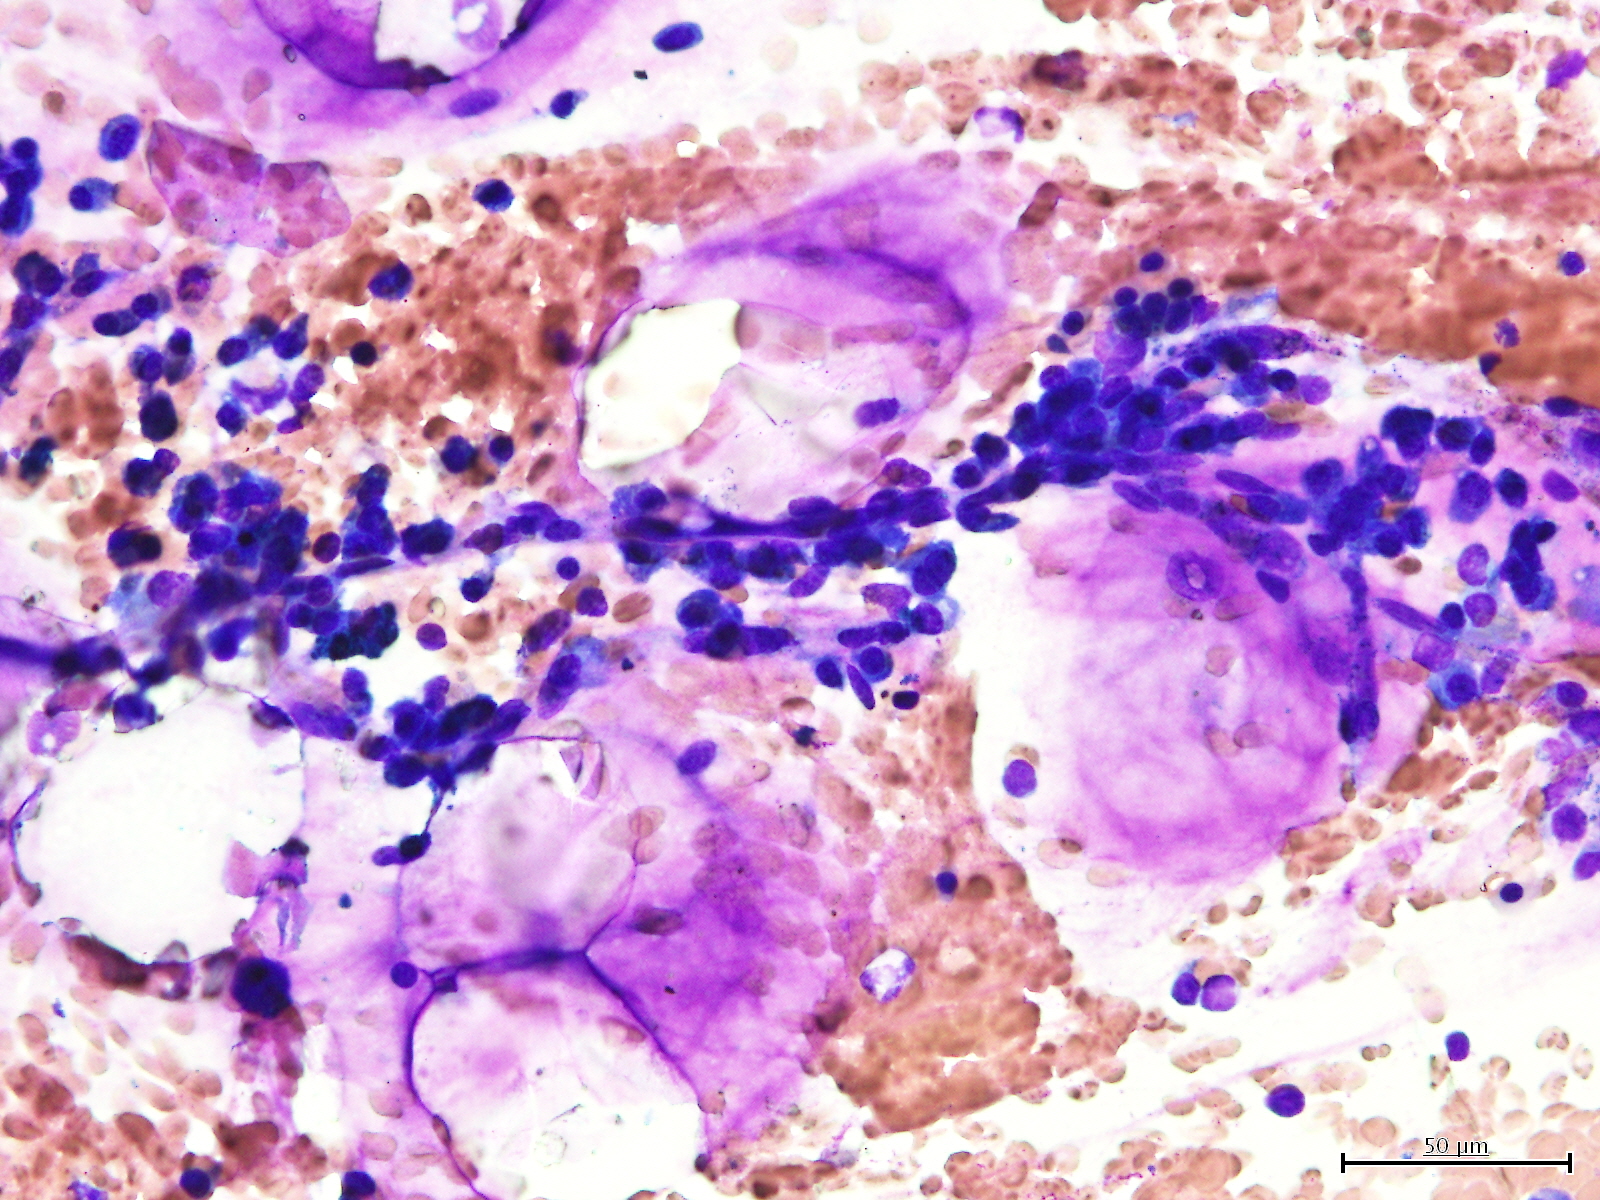

赤血球は骨髄で造血幹細胞から作られるが、その分化・成熟には骨髄においてマクロファージが大きく関わっている。 骨髄において、赤血球の幼若な段階である赤芽球はマクロファージを中心にその回りを取り囲むように数個から数十個が集団で寄り集まっている。中心に存在するマクロファージは赤芽球に接し、ヘモグロビンの合成に不可欠な鉄や細胞の生育に必要な物質を供給し、成熟をコントロールし、また脱核させた核の処理や、不要になった赤血球細胞の除去にも関与している 。 この、骨髄内においてマクロファージを中心に赤芽球が集まり、赤血球の形成に関わっている細胞集団を赤芽球島もしくは赤芽球小島という。